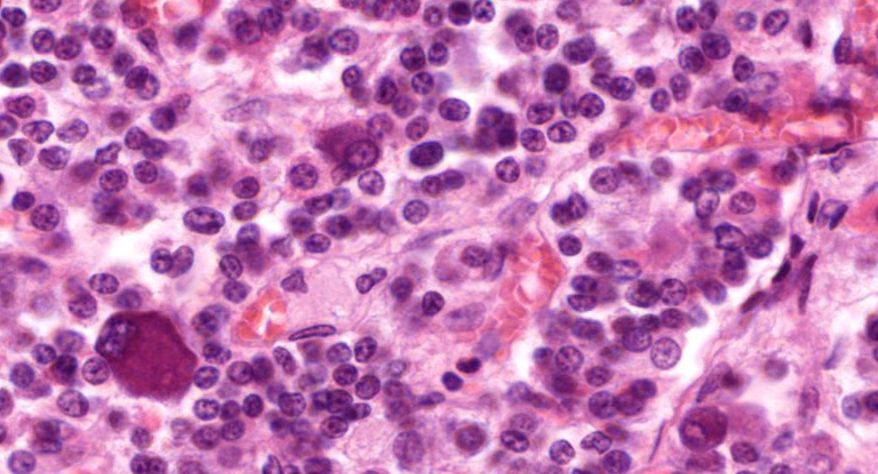

低倍镜观察:1. 被膜:由薄层结缔组织组成。2. 实质:由许多大小不等的滤泡构成。滤泡壁是单层立方上皮细胞,滤泡腔内充满粉红色匀质胶状物,滤泡之间的结缔组织内有丰富的血管。高倍镜观察:1. 滤泡:滤泡壁的单层滤泡上皮细胞一般呈低柱状或立方状,胞质着浅色,细胞核呈圆形。滤泡腔内充满了粉红色匀质胶质。2. 滤泡旁细胞:体积较大,呈圆形或椭圆形;细胞核较大,呈圆形,着色较浅,细胞质染色也较浅。细胞或嵌在滤泡壁上或成团分布于滤泡之间。3. 间质:由结缔组织组成。位于滤泡之间。其中含有丰富的毛细血管及三五成群的滤泡旁细胞。

1.全景图

2.滤泡

3.滤泡上皮细胞

4.胶质

5.滤泡旁细胞1

7.滤泡旁细胞2